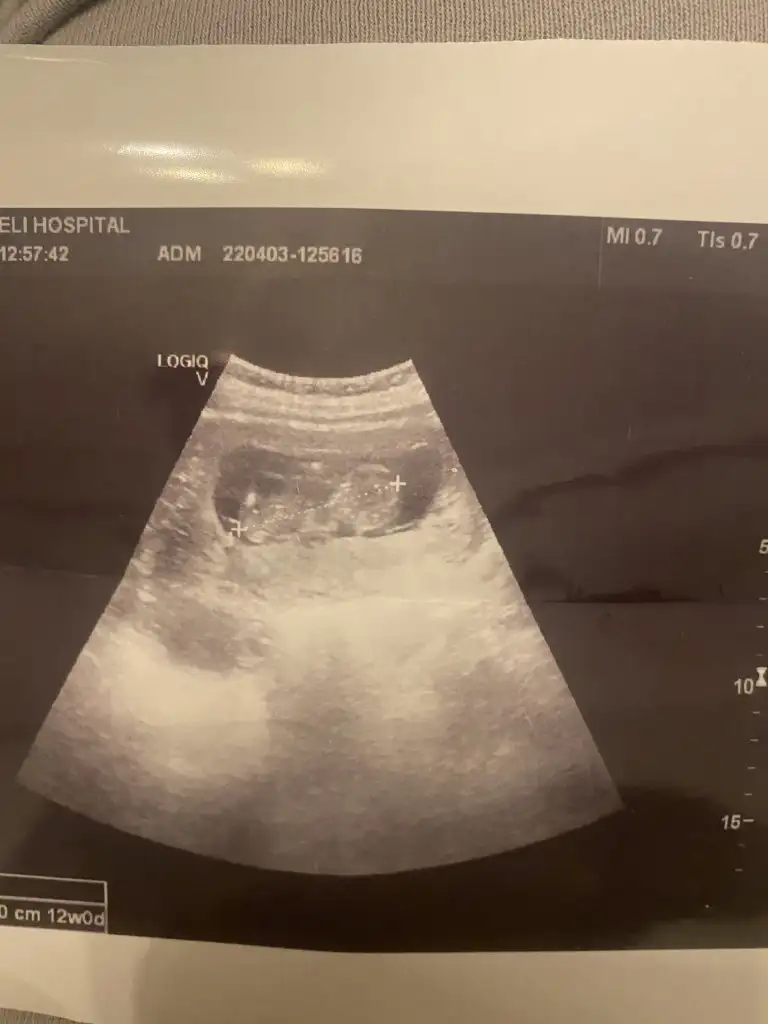

Bana da tahminde bulunur musunuz ? Sağ mı sol mu ben hiç anlamıyorumCanim eger Sol yerlesimli ise kiz sag ise erkek kafasi soldaydi hep benimkinin kizim olacak Insallah

Erkek görünüyorMerhaba kızlar rica etsem benim bebeğime de bir bakar mısınız12+1Eki Görüntüle 3043282

Bencede erkek canım.Allah sağlıkla kucağına almayı nasip etsinMerhaba kızlar rica etsem benim bebeğime de bir bakar mısınız12+1Eki Görüntüle 3043282